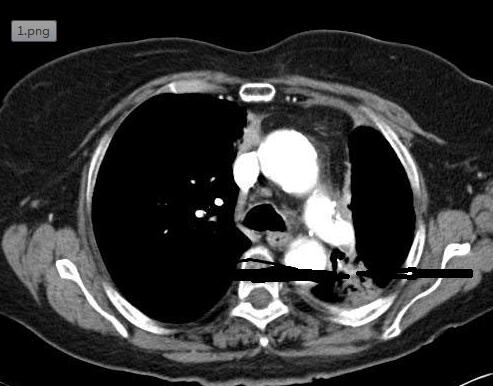

肺癌通常比较隐秘,直到晚期才会出现明显症状。在大多数患者中,需要高度的怀疑指标来正确判断这种疾病。此时,体重降低、咯血和二手烟暴露史,以及低程度发热和不规律的肺部评估,都需要对肺癌进行调查。之后,CT显示,左上叶有1.3 cm的复合结节(图1)。

图1